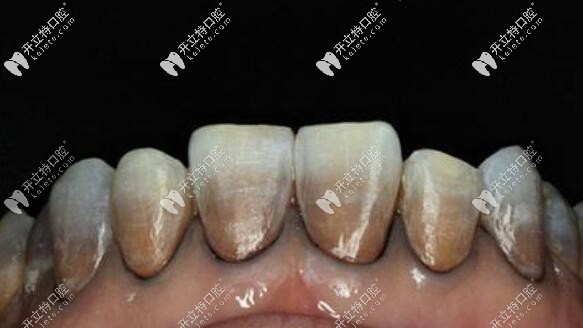

重度四環(huán)素牙照片↓↓↓

瑞典全瓷冠對圖片中的重度四環(huán)素牙有不錯(cuò)效果